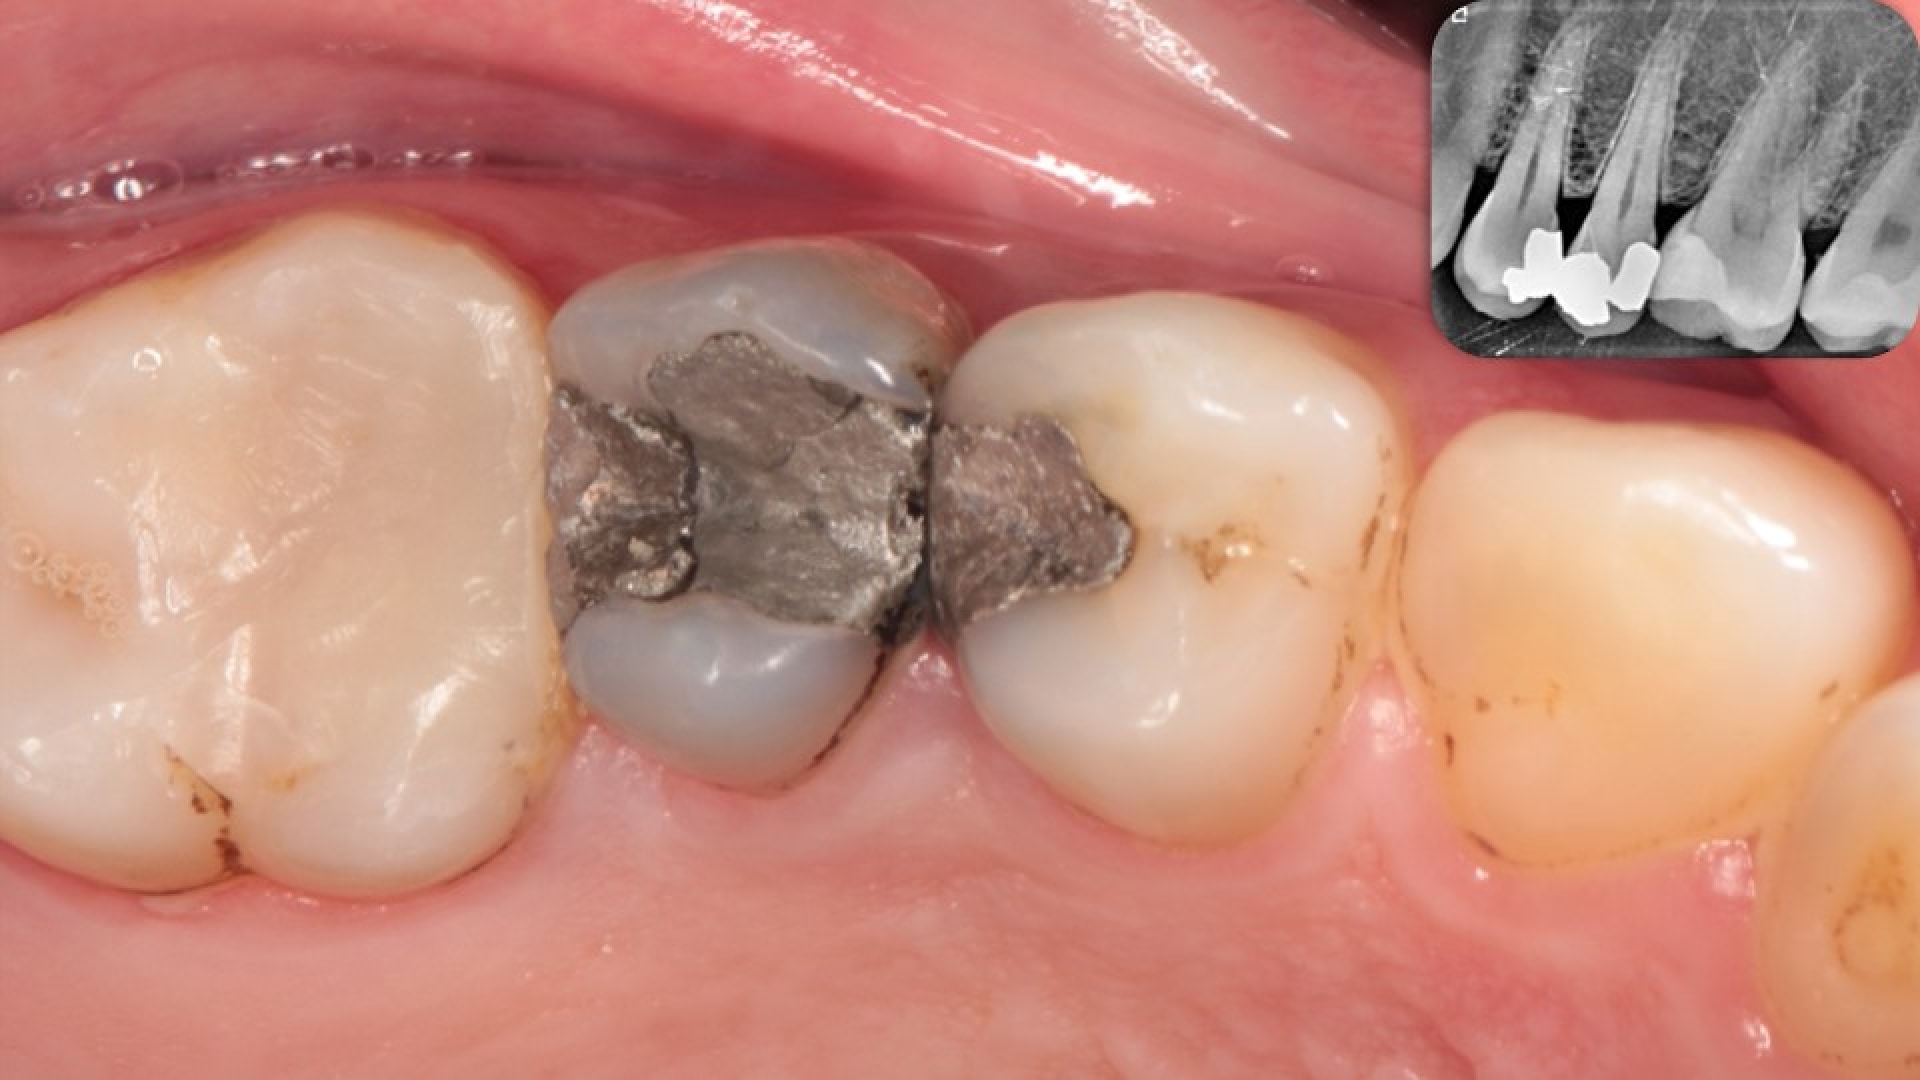

Direct or Indirect? Picture

By Dr.Dina EzzeldinAdded on January 2026

Direct or Indirect?

That's the question

Patient presented with back to back amalgam restorations in the upper right first and second premolars. Patient suffered from discomfort & transient p...

Read More